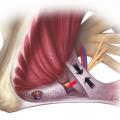

Névralgies pudendales

Le diagnostic de névralgie pudendale (NP) est clinique et comprend deux conditions incontournables  : la douleur est spontanée, de forme neuropathique à type de brûlures, coups d’aiguille, fer rouge, décharges électriques. Elle répond au score du questionnaire DN4.1 C’est le plus souvent une douleur violente sur l’échelle…